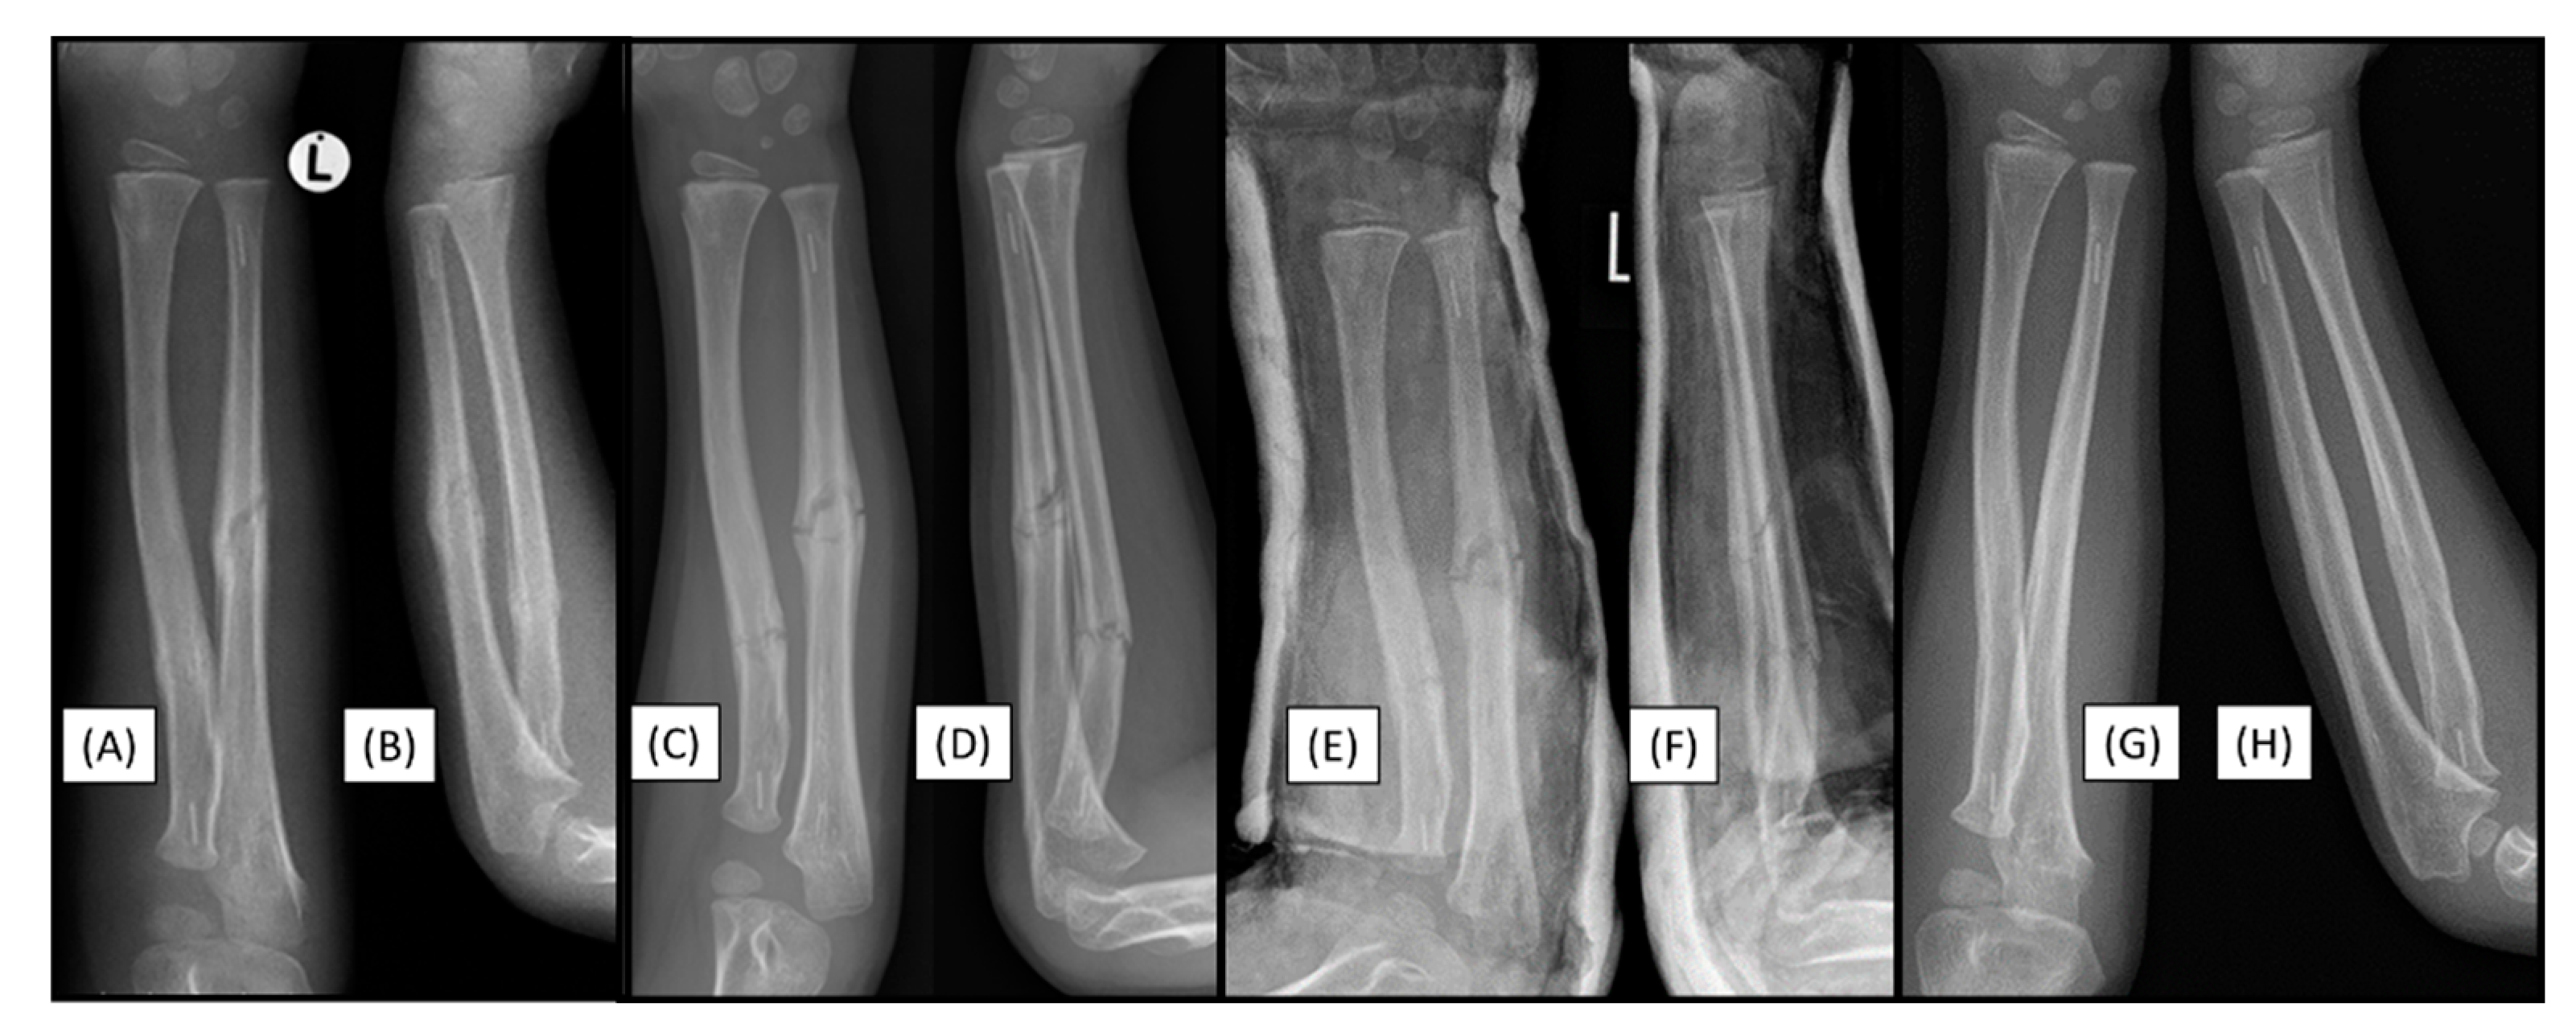

3.2. Case 2: Narrow Medullary Cavity

A 14-year-old boy was scheduled for surgical treatment due to a displaced, unstable middle-third forearm fracture (AO type: 22-D/2.1.). Preoperative measurements indicated that the medullary cavity diameter was narrow(Figure 2(A-C)). Although this patient case did not involve an implant-related complication, it directly relates to the challenges associated with the surgical procedure. Despite multiple attempts, the introduction of the 2.7 mm dilator failed during the preparation of the radius medullary cavity. The radius was stabilized with a two mm elastic nail, while the ulna was stabilized with a 2.5 mm nail (Figure 2(D-E)). As with any surgery, preoperative planning is crucial, including measuring the diameter and shape of the medullary cavity. Several publications address the morphology of the pediatric medullary cavity, which can influence the choice of treatment method. In our case, we were unable to prepare the medullary cavity, thus making the use of absorbable IM implants unfeasible.

Figure 2. Preoperative X-rays from AP (A) and lateral (B) aspects of a both-bone diaphyseal forearm fracture. A magnified image shows the measurement of the medullary canal both distal and proximal to the fracture (C). Both bones were stabilized with elastic nails, visible from AP (D) and lateral (E) views.